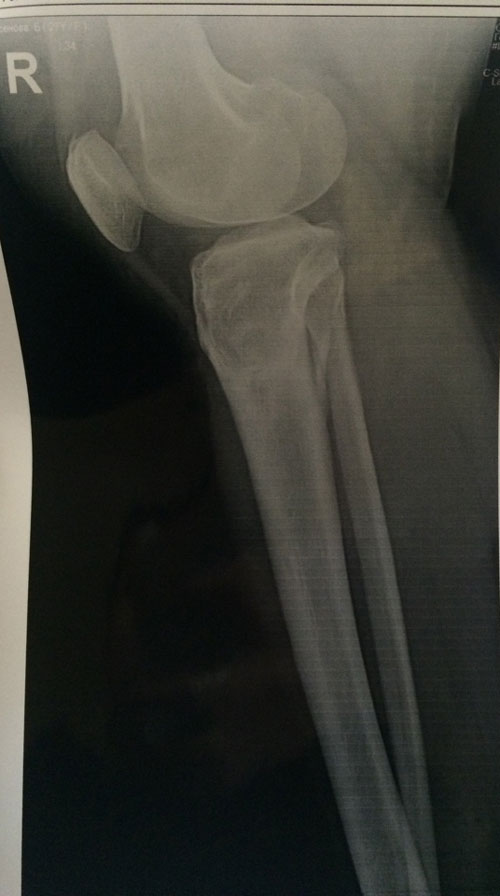

Диагноз: ахондроплазия, варусная деформация обеих голеней 155 градусов.

Исходник.